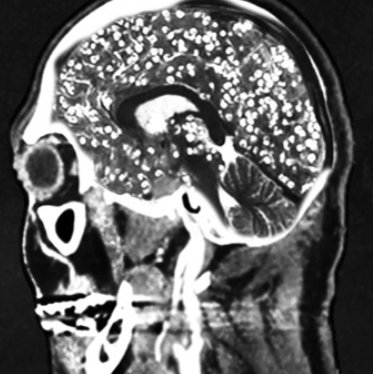

'돼지고기 촌충'이라 불리는 갈고리촌충의 유충은 혈액을 타고 뇌에 침범해 두통과 발작을 일으키기도 한다. /사진= 유튜브 Chubbyemu]